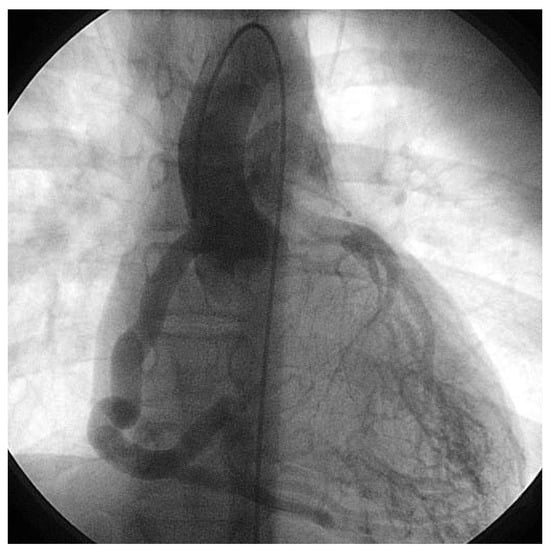

An otherwise healthy 13-year-old girl was referred to the pediatric cardiology outpatient clinic for evaluation of a newly observed systolic murmur. She was normally physically active without symptoms on exertion except for one episode of syncope two months earlier. She then was riding a bike and on climbing off the bike she was observed to hyperventilate, had parestesias of both hands followed by a short loss of consciousness. Family history was negative for any cardiac event. Clinically the systolic murmur was judged a functional ejection murmur but an Echo was done and revealed an enlarged (6 mm) right coronary artery (Figure 3) with huge collaterals especially in the septal region (Figure 4), the origin of the left coronary artery was seen in the pulmonary trunk with turbulent retrograde flow in the color Doppler (Figure 5). LV ejection fraction was 68% but the LV was slightly dilated with a mild mitral regurgitation. Cardiac catheterisation confirmed the suspected anomalous origin of the left coronary artery from the pulmonary trunk (Figure 1 and Figure 2), the patient was advised to undergo surgical correction with reimplantation of the left coronary artery in the aorta.

Figure 4. Modified parasternal long axis echo view showing several turbulent flows in projection on the interventricular septum.

Figure 5. Superior short axis echo view showing turbulent flow draining into the pulmonary artery trunk above the valve and originating from the apparent region of the left coronary artery.